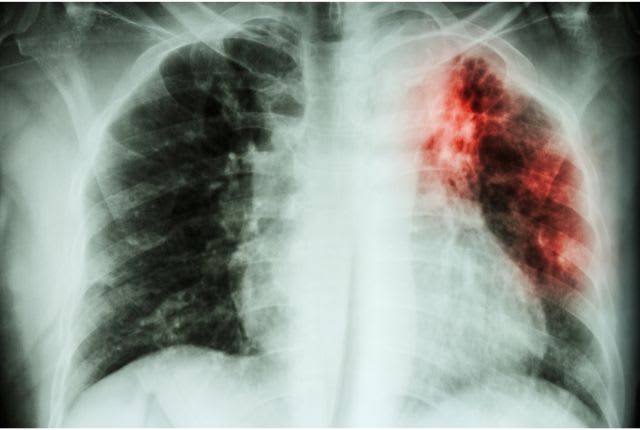

Fibrose pulmonaire

La fibrose pulmonaire est une maladie chronique qui affecte les poumons. Elle touche principalement les personnes aux alentours de 60 ans.

Les causes de la fibrose pulmonaire ne sont pas toujours identifiées. Ce que l’on observe, c’est une inflammation du tissu interstitiel qui soutient les alvéoles pulmonaires, perturbant ainsi les échanges gazeux du poumon. Une pathologie qui peut mener à une détresse respiratoire aiguë. Découvrez quels sont les symptômes, les causes et les traitements de la fibrose pulmonaire.

L’air inspiré passe par les bronches et leurs extrémités, les bronchioles, pour être distribué aux poumons. Aux extrémités des bronchioles se situent les alvéoles pulmonaires, formées d’un tissu pulmonaire et chargées de réaliser les échanges gazeux du poumon. Or en cas de fibrose pulmonaire, ce tissu interstitiel est malade, cicatriciel, se rigidifie. Du fait de cette inflammation du tissu interstitiel, les poumons ne peuvent plus assurer correctement les échanges gazeux entre l’extérieur et le sang. On distingue 4 types de fibrose pulmonaire : la fibrose pulmonaire idiopathique (de cause inconnue), la fibrose pulmonaire médicamenteuse, la pneumoconiose, la pneumopathie d’hypersensibilité. C’est une pathologie rare.